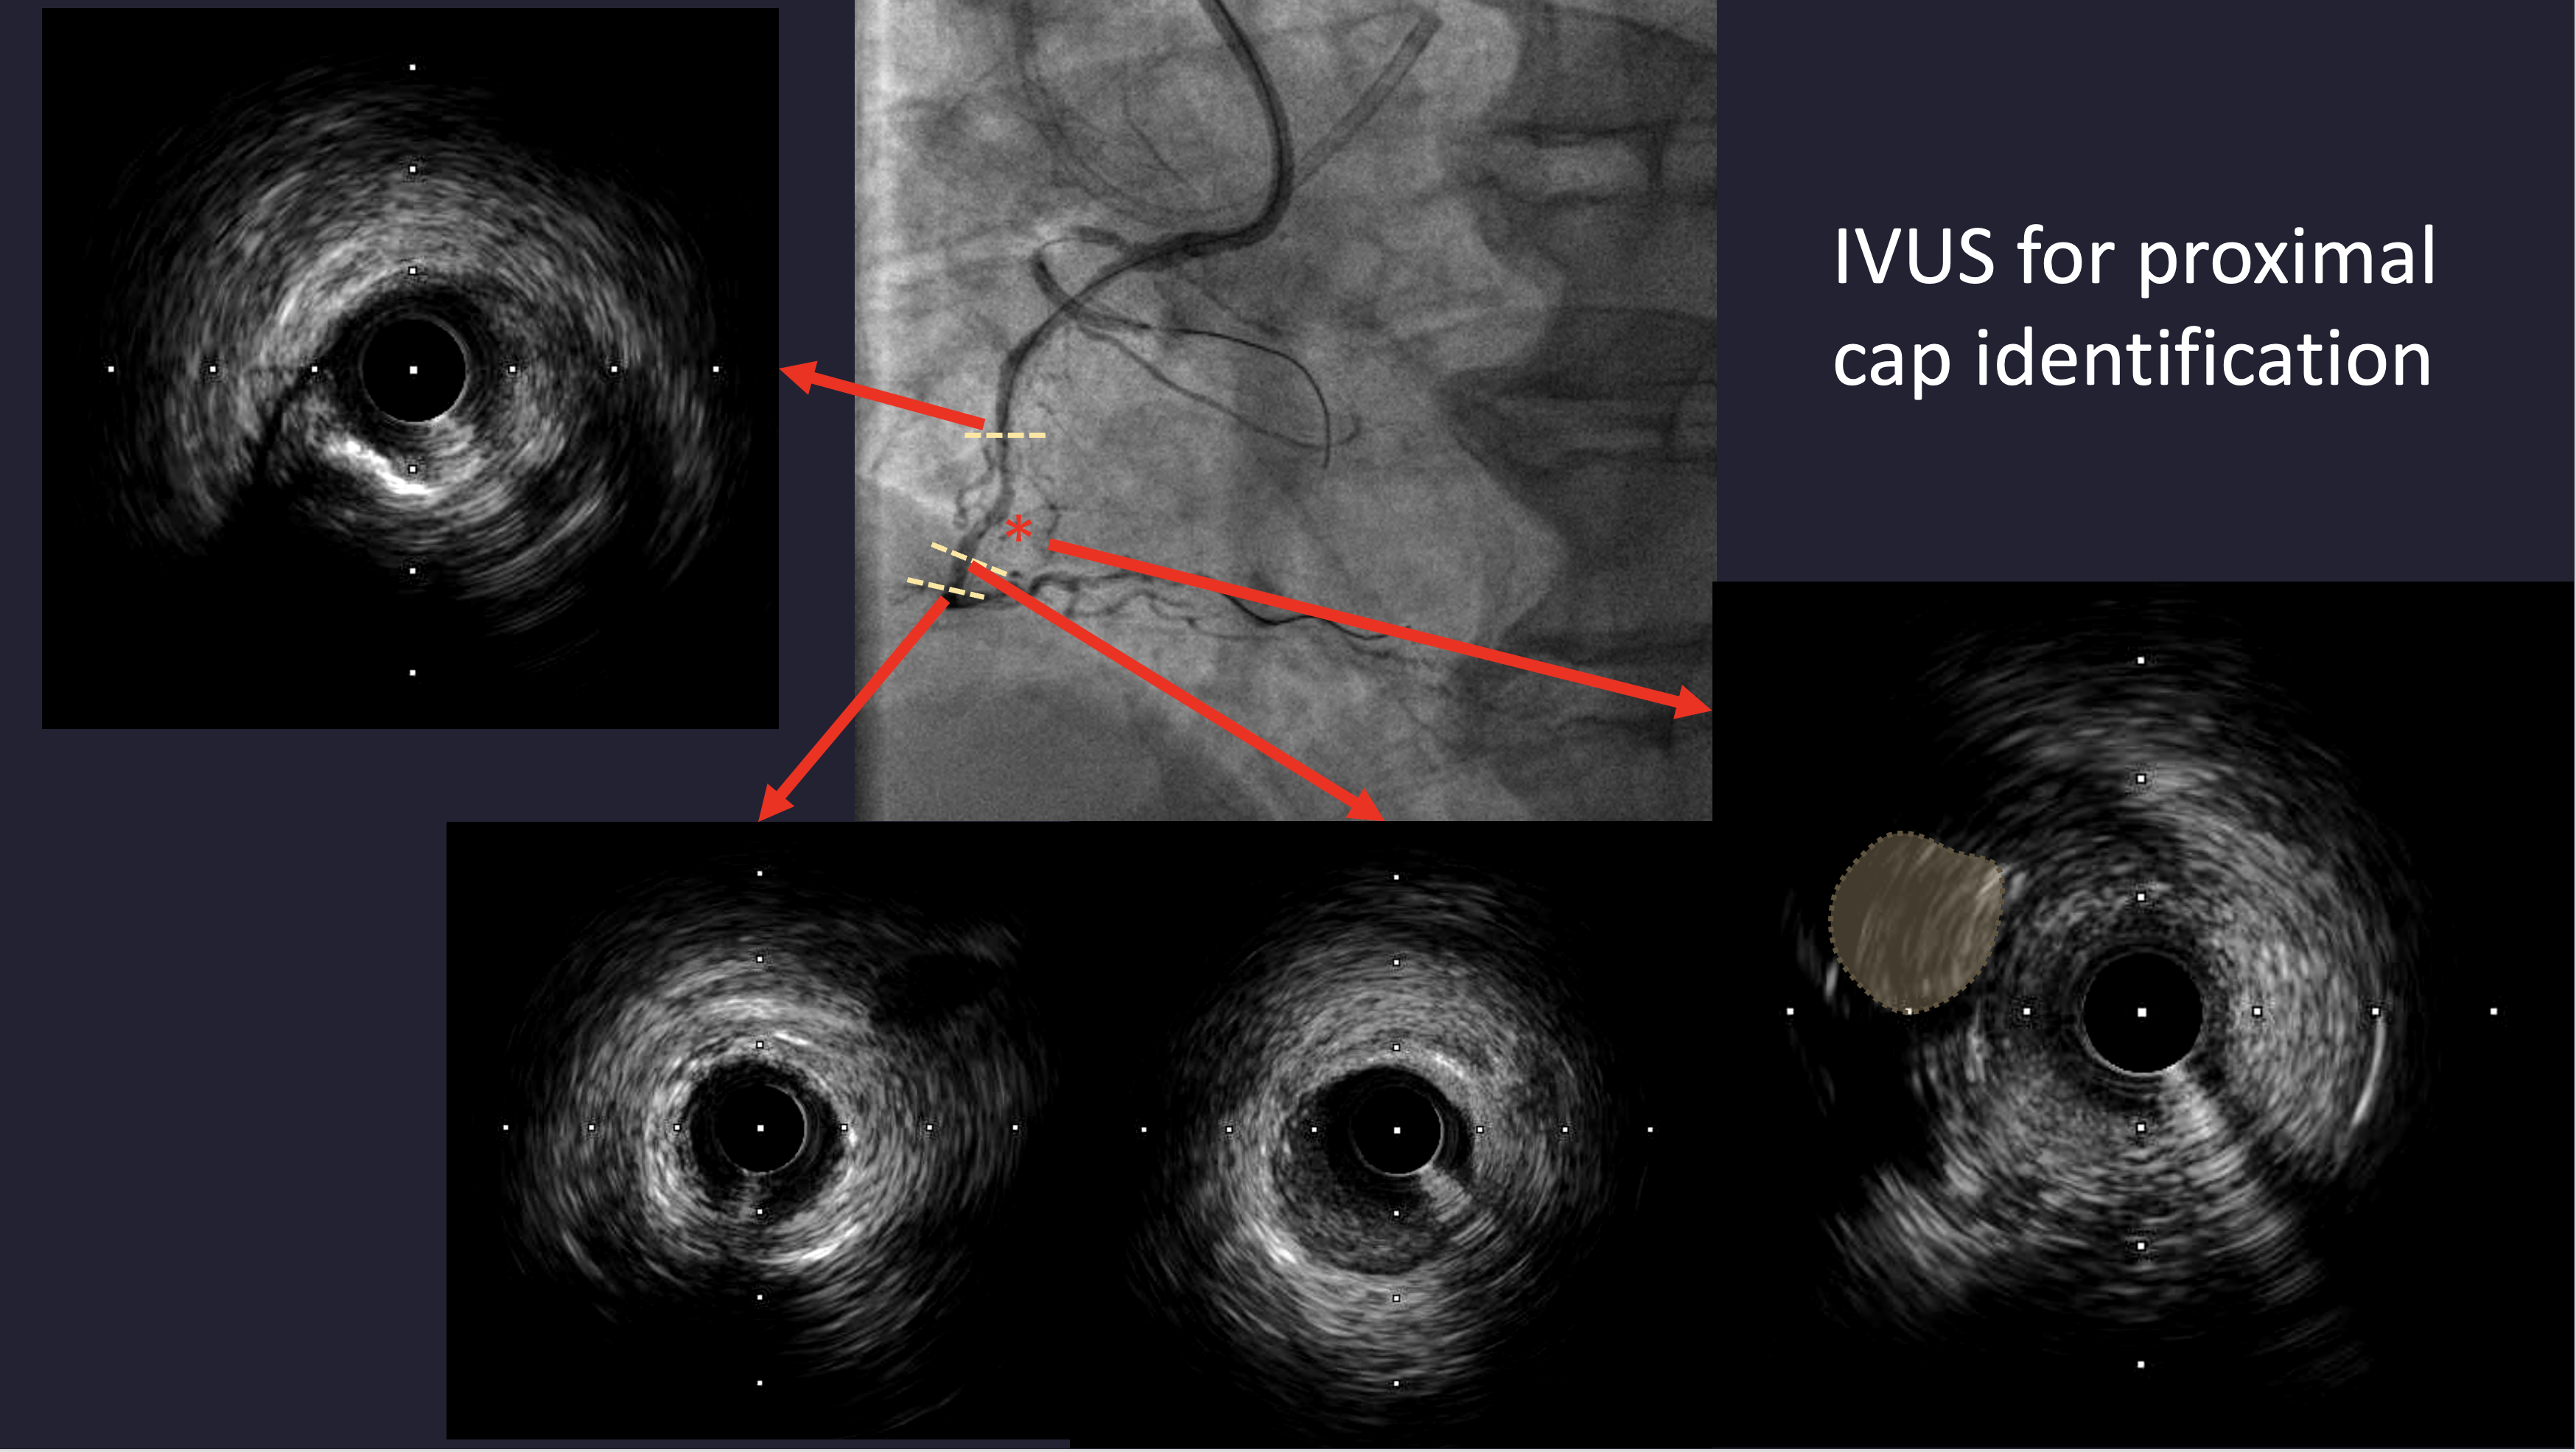

Left coronary angiography revealed mild plaquing in the LAD without significant stenosis and a critical lesion in the LCX. RCA angiography demonstrated a chronic total occlusion with a blunt proximal cap, lesion length greater than 20 mm, and distal bifurcation into the PLV and PDA. Collateral circulation from septal branches and the distal LAD to the PDA was identified.

Dual arterial access was obtained for dual injection. The initial antegrade approach was attempted using a SION Blue wire and a 2.0 ¡¿ 20 mm anchor balloon under IVUS guidance to identify the proximal cap, but antegrade wiring with UB3, Gaia Second, and Gaia Third failed to reach the distal cap. A retrograde approach through the distal septal branch to the PDA was then performed using a Finecross microcatheter and SION Black wire, followed by UB3 and Gaia Second/Third wires. Reverse CART was successfully achieved with a 1.5 ¡¿ 20 mm balloon at the mid RCA, and wire externalization with RG3 was performed through a Guide Extension Catheter. POBA was done with 1.5 and 2.0 mm balloons, followed by DES implantation (2.5 ¡¿ 48 mm and 3.5 ¡¿ 33 mm). After the final RCA angiogram, the patient developed severe hypotension. Echocardiography revealed minimal pericardial effusion and LAD territory akinesia. LAD angiography showed acute total occlusion. Immediate balloon angioplasty and aspiration thrombectomy were performed, and IVUS was used to identify the cause of LAD closure. IVUS revealed a dissection flap in the mid LAD, suspected to be iatrogenic due to the cutting effect of the externalized RG3 wire despite microcatheter protection. An additional DES (3.0 ¡¿ 48 mm) was deployed in the LAD, restoring TIMI 3 flow. The patient stabilized hemodynamically after intervention.

This case emphasizes the utility of IVUS in identifying the CTO proximal cap and confirming true lumen after Reverse CART. However, it also demonstrates a rare but serious complication—iatrogenic coronary dissection likely caused by the cutting effect of the externalized RG3 wire, even when protected by a retrograde microcatheter. Operators should remain vigilant for hemodynamic instability following complex CTO procedures and promptly evaluate for potential non-target vessel injury to ensure rapid management and optimal outcomes.